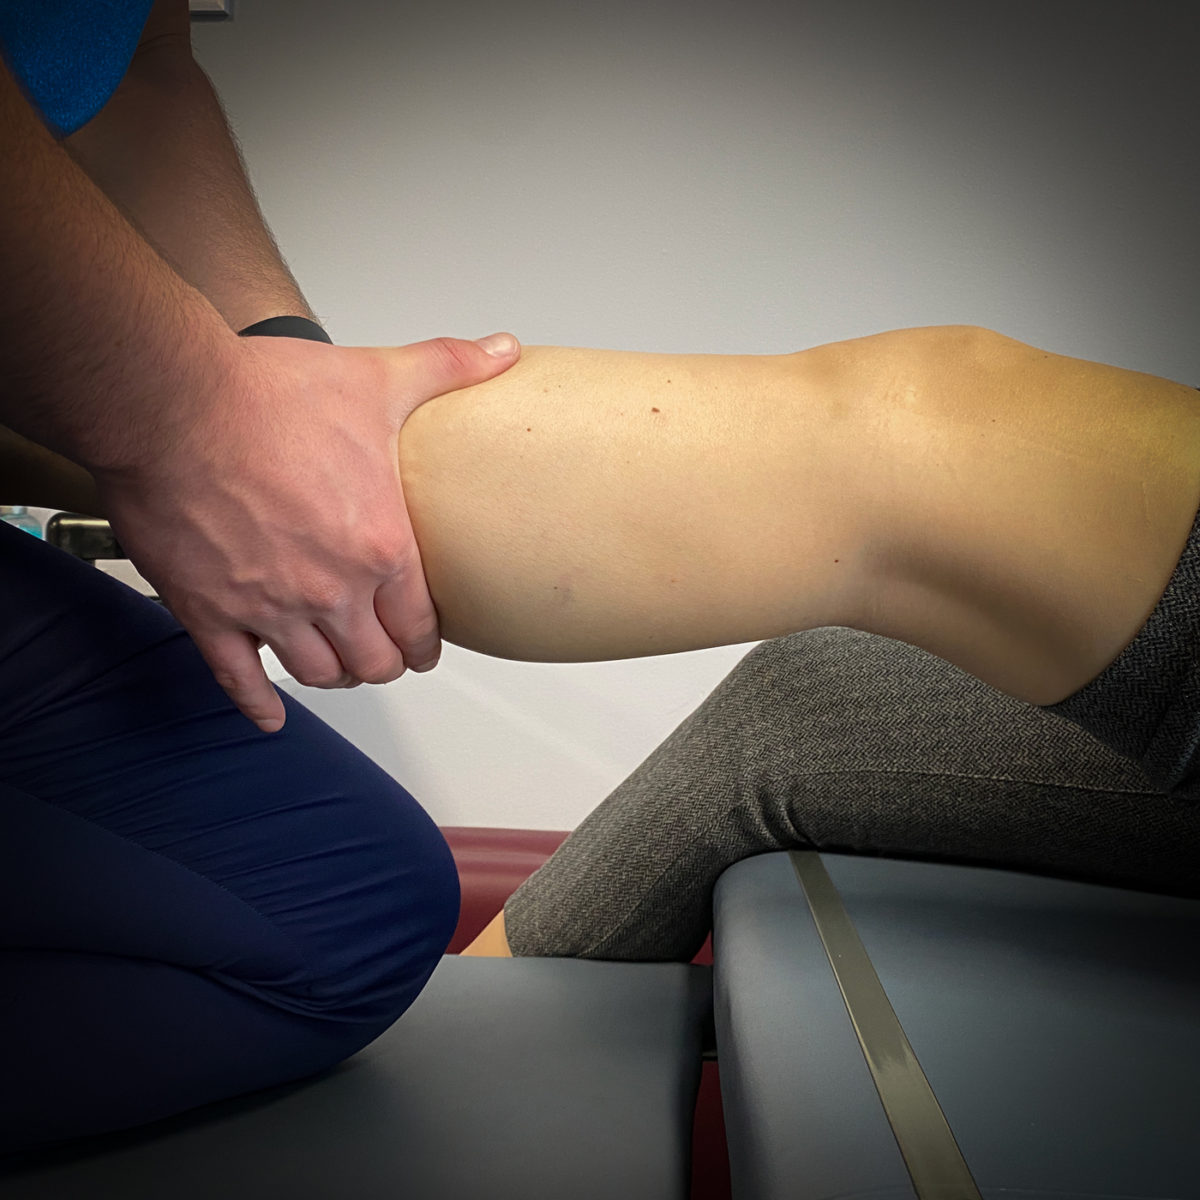

MANUAL THERAPY

Manual therapy is a hands-on, one-on-one approach with your physical therapist that includes joint mobilizations, manipulations, stretching, massage therapy, and passive movement of muscles and joints. Your therapist will guide you how to move against targetted resistance to improve muscle function. Manual therapy can also include lymph drainage, joint traction, and trigger point release therapy.